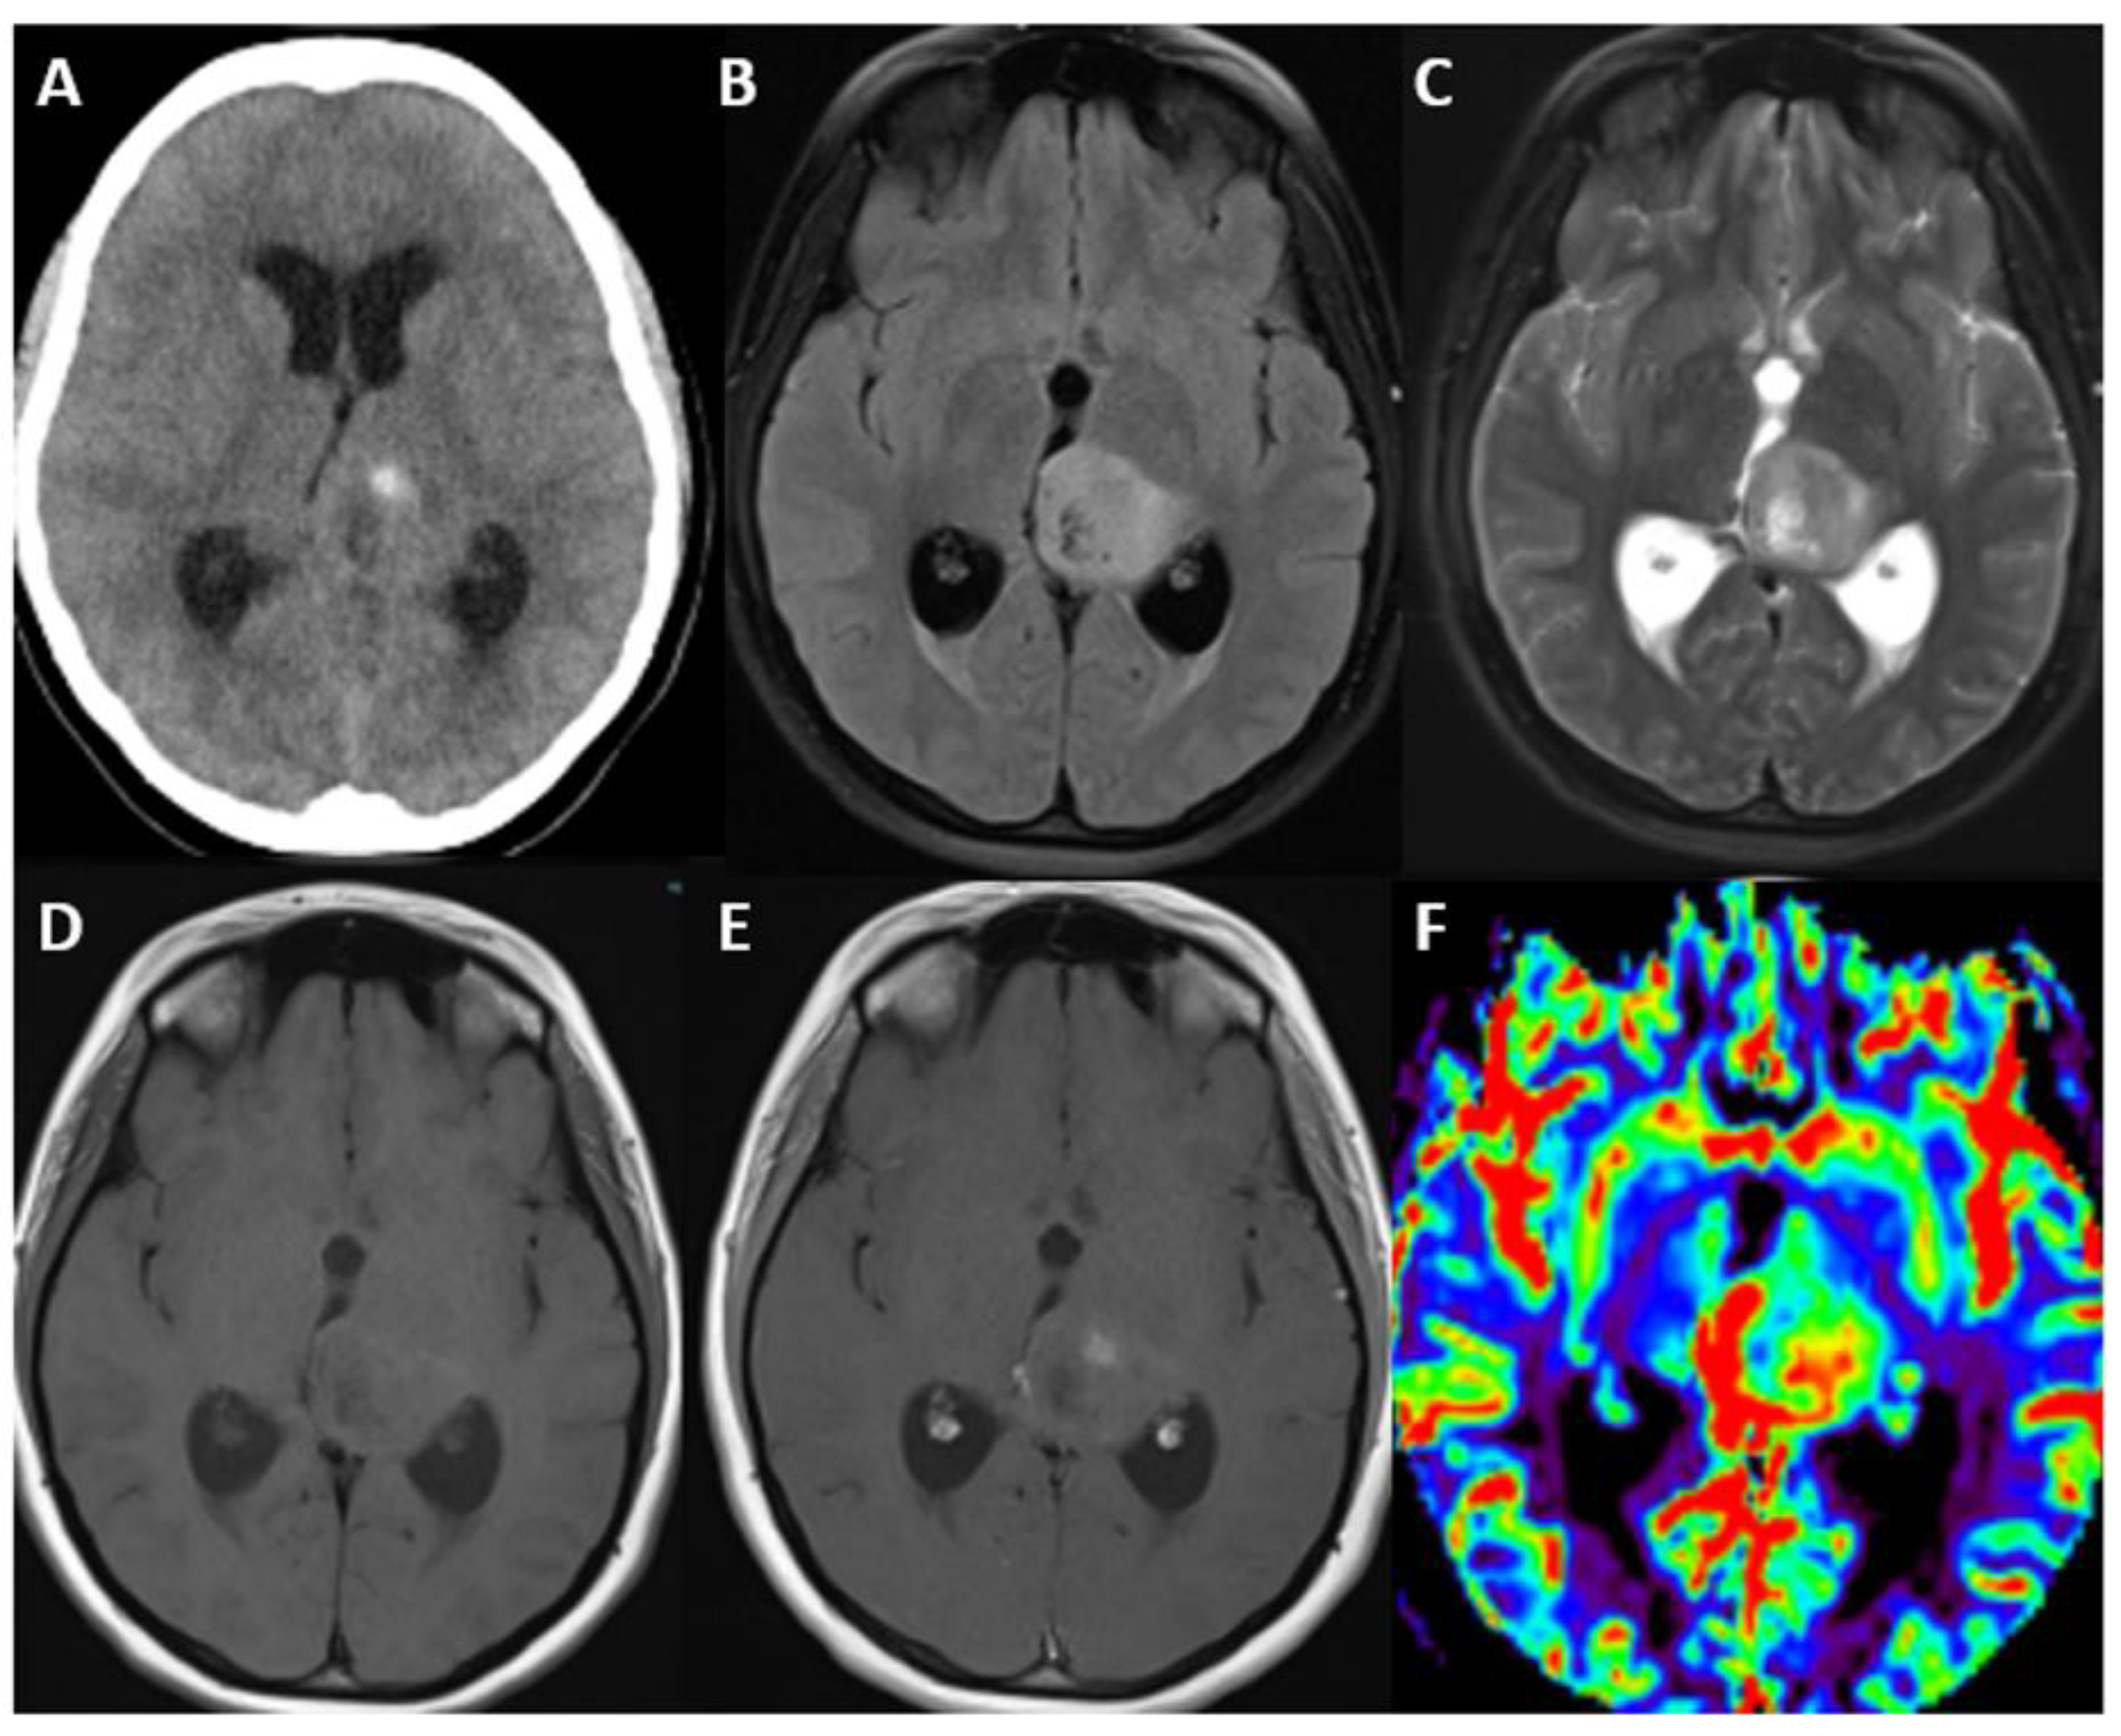

5. Glioblastoma, IDH-Wildtype

5.1. Update

Brief Genetic Overview of Relevance of Molecular Markers

5.2. Clinical Features and Localization

5.3. Imaging

| Glioblastoma, IDH-wildtype | IDH-wildtype, TERT promotor, +7/−10 chromosome copy number changes, EGFR | Only IDH-wildtype no IDH-mutant, | Inherent heterogeneity, heterogeneously enhancing, sometimes ring- enhancing around central necrosis, surrounding T2/FLAIR signal, edema and mass effect, increased rCBV, surrounding infiltration. |

| IDH-wildtype astrocytic tumors with 1 of following: Microvascular proliferation or necrosis, TERT promotor mutation, or EGFR gene amplification, +7/−10 chromosome copy number changes. |